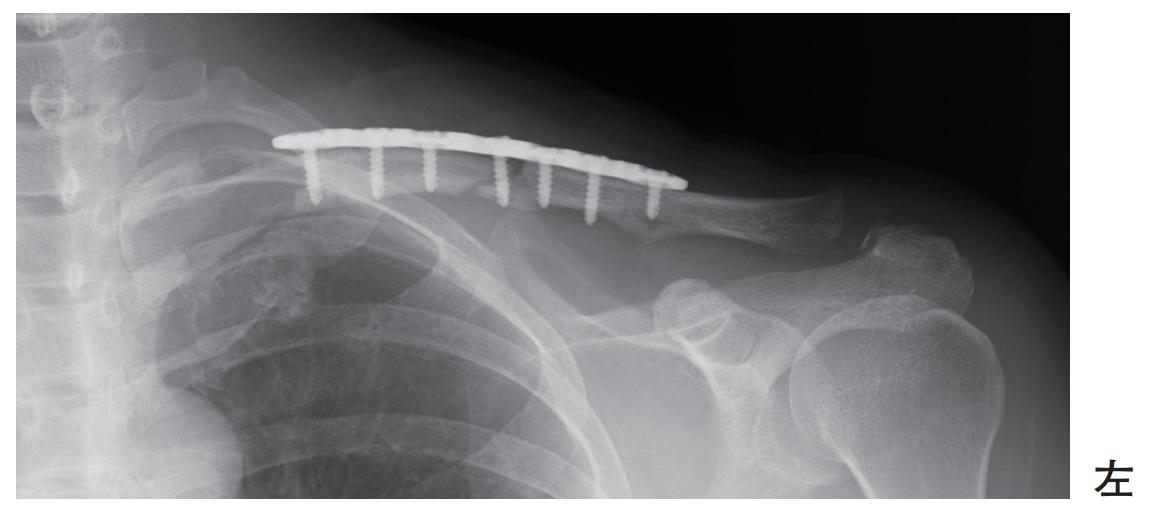

53歳の女性。自転車走行中に転倒受傷し、鎖骨骨幹部骨折に対して観血的整復固定術が施行された。術後のエックス線写真を別に示す。

術後翌日の患側の理学療法で正しいのはどれか。